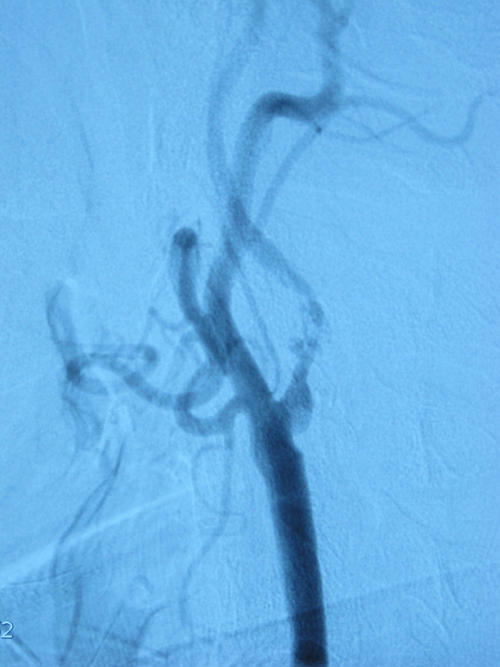

患者二:徐某某,男,65岁,因发作性头晕一个月入院,既往有晕厥病史,高血压病史20年,糖尿病病史3年,入院后行DSA检查示:左侧颈内动脉重度狭窄,约95%,左锁骨下环状狭窄80%。手术指征明确,于12于17日顺利手术。

患者三:陈某某,男性,61岁,主因突发左上肢无力一小时入院,既往体健,长期吸烟饮酒,TCD显示:右颈内动脉颅外段重度狭窄,颈部彩超示:颈内动脉开口处重度狭窄,85%。患者同时合并右侧后交通动脉瘤,手术顺利。